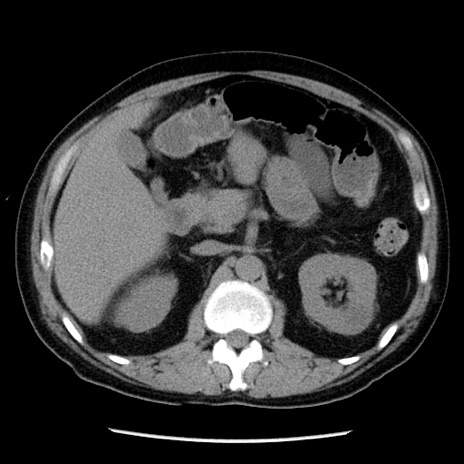

症例29(横断像)

【症例】40歳代男性

【現病歴】2日前から胃痛あり。徐々に周期的な激痛に変化した。本日になっても激痛があるため受診。

【身体所見】意識清明、BT 38-39℃台あり、腹部:膨満、やや硬、右下腹部に圧痛あり。

【データ】WBC 8500、CRP 23.26